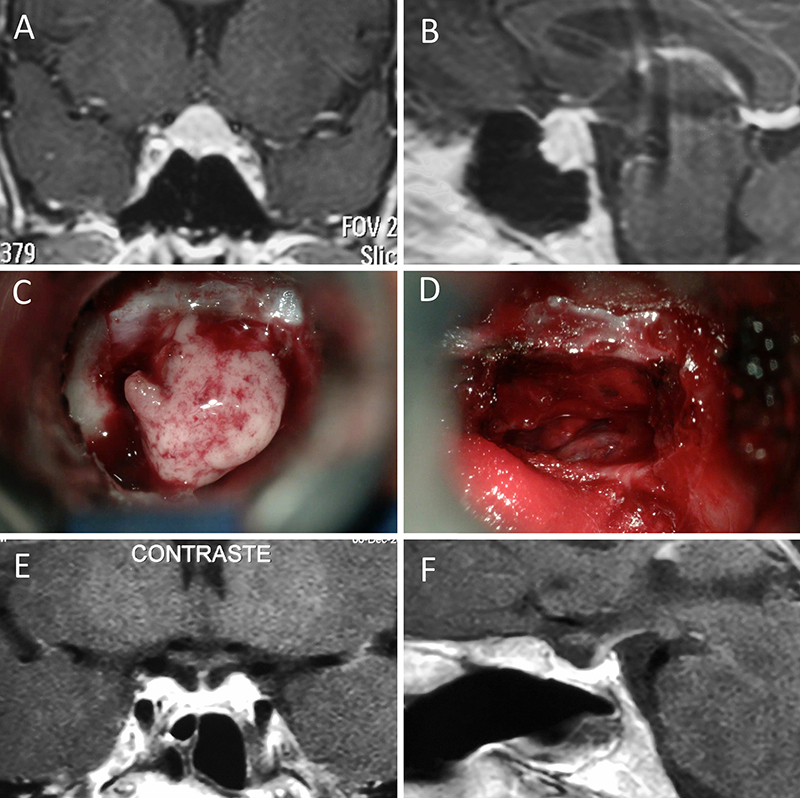

Figura 1: Macroadenoma no funcionante en mujer de 65 año s. Se decidió la cirugía tras evidenciarse crecimiento en los controles. Evolucionó favorablemente desde el punto de vista clínico-radiológico. A-B: RM preoperatoria; C-D: intraoperatorio; E-F: RM postoperatoria.